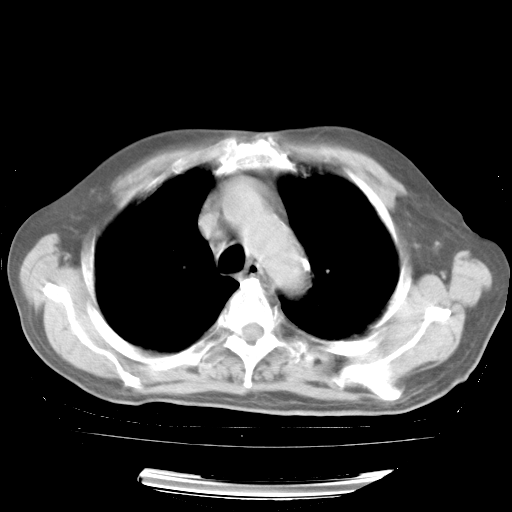

4月28日肺部CT

个人阅读4.14日肺部CT平扫:纵隔窗无异常,但肺窗示:双下肺内、后基底段有片絮状侵润影,部位以后基底段为著,以间质改变为主,呈急性肺泡炎征像,和首次住院影像学有相似之处。仅是个人读片,明日请相关专家再读片哈。其它建议同上。